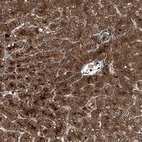

Immunohistochemical staining of human liver shows strong cytoplasmic positivity in hepatocytes.